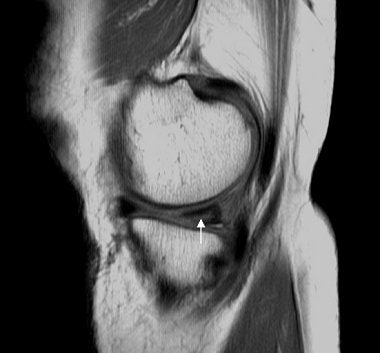

| Above, sagittal proton density-weighted MR image obtained through the posterior horn of the medial meniscus shows linear increased signal (arrow) extending to the inferior articular surface of the meniscus. Below, longitudinal ultrasonography obtained through the posterior horn of the medial meniscus shows a discrete hypoechoic cleft (arrowheads) extending to the tibial articular surface of the hyperechoic meniscus. Images courtesy of Dr. Gi-young Park. |